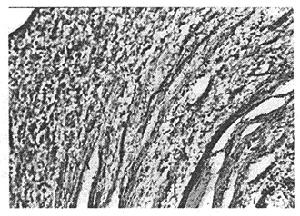

IPT的基本病理特徵是炎性增生腫塊,主要由纖維基質和漿細胞為主的各種慢性炎性細胞浸潤所構成的局灶性病變,多呈圓形或橢圓形,直徑1~25cm,文獻報導最大者為25cm×25cm×13cm 近年因B超等影像技術普遍套用而易被發現,多為直徑2~4cm左右的小型病灶。IPT多見於肝臟表面,可與腹壁 膈肌和周圍組織有炎性粘連;少數可位於肝實質深部或第一、二肝門附近, 肝臟炎性假瘤具有完整包膜,界限清楚,堅硬、 質韌,其切面光滑平整,呈灰白色或黃色。鏡下可見漿細胞、組織細胞 ,成纖維細胞及環狀細胞等各種炎性細胞 病變周圍有明顯炎症及纖維組織增生 有的可能是大量肝細胞壞死,但液化少見。肝臟通常無肝硬化。

炎性假瘤的細胞成分,在不同病例各不相同。Someren根據其細胞成分將IPT分為3種組織類型:①以瀰漫緻密的纖維增生為主的稱為硬化性假瘤;②以組織細胞占優勢者稱黃色肉芽腫;③以漿細胞為主的稱為漿細胞肉芽腫。尚不明確這些組織類型與臨床過程有何密切的相關性。